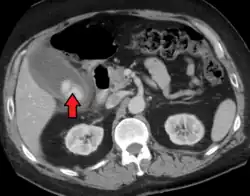

| Acute cholecystitis as seen on CT. Note the fat stranding around the enlarged gallbladder. | |

Right upper quadrant abdominal ultrasound is most commonly used to diagnose cholecystitis.[1][25][26] Ultrasound findings suggestive of acute cholecystitis include gallstones, pericholecystic fluid (fluid surrounding the gallbladder), gallbladder wall thickening (wall thickness over 3 mm),[27] dilation of the bile duct, and sonographic Murphy's sign.[13] Given its higher sensitivity, hepatic iminodiacetic acid (HIDA) scan can be used if ultrasound is not diagnostic.[13][14] CT scan may also be used if complications such as perforation or gangrene are suspected.[14]

Acute cholecystitis with gallbladder wall thickening, a large gallstone, and a large gallbladder- Significant gallbladder wall thickening[28]